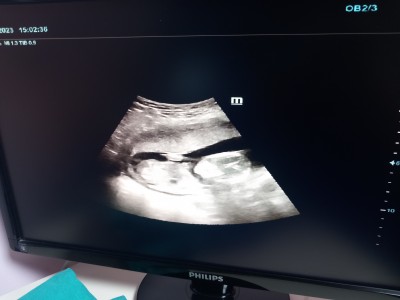

12 haftalıkken doktora gittim erkek dedi 13te yine erkek dedi 15te devlete gittim başka  bir doktor bacakları kapalı kız olabilir dedi emin değilim dedi 16+5 özele gittim  erkek dedi ćook merak ediyorum ya

16 haftada erkek dediyse doğrudur çünkü o haftada pipisi tam belli oluyor büyüdüğü için

İki defa erkek dediler iki ayrı doktor  ama devlet hastanesindeki kafamı  karıştırdı  bacakları kapalı  kız olabilir demişti

Üç kız doğurdum hep bulantılarim vardı kusma falan bu hamilelikte 17 haftalık oldum hiç kusmadım herkes farklı erkek hissediyorum ama doktor kafamı  karıştırdı işte